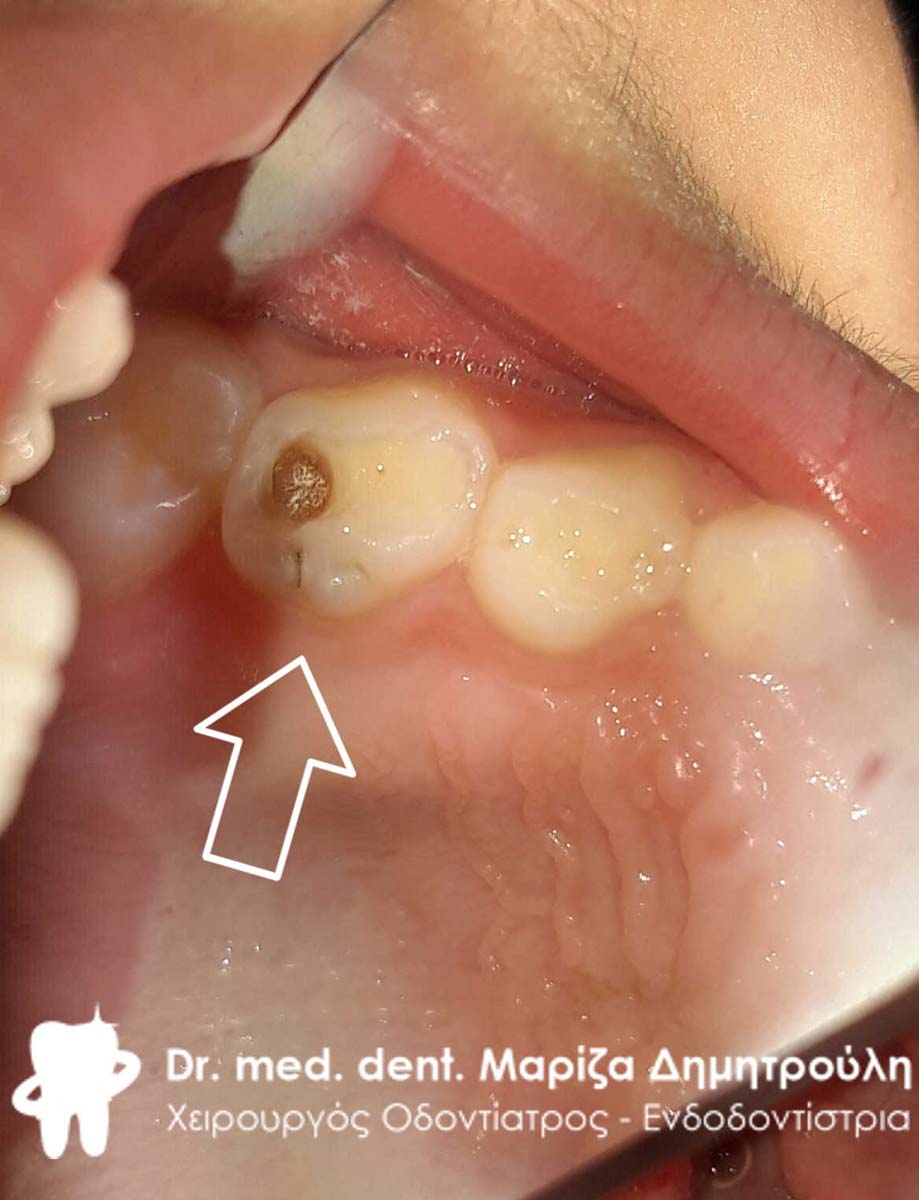

Περιστατικό – Σφράγισμα παιδικού δοντιού

Αγόρι ηλικίας 9 ετών παραπονιόταν οτι πονούσε στην αριστερή πλευρά της κάτω γνάθου. Μετά την κλινική εξέταση διαπιστώθηκε η ύπαρξη μιας τερηδονικής κοιλότητας, η οποία αποκαταστάθηκε με λευκό σφράγισμα σύνθετης ρητίνης.

ΠΡΙΝ

ΜΕΤΑ